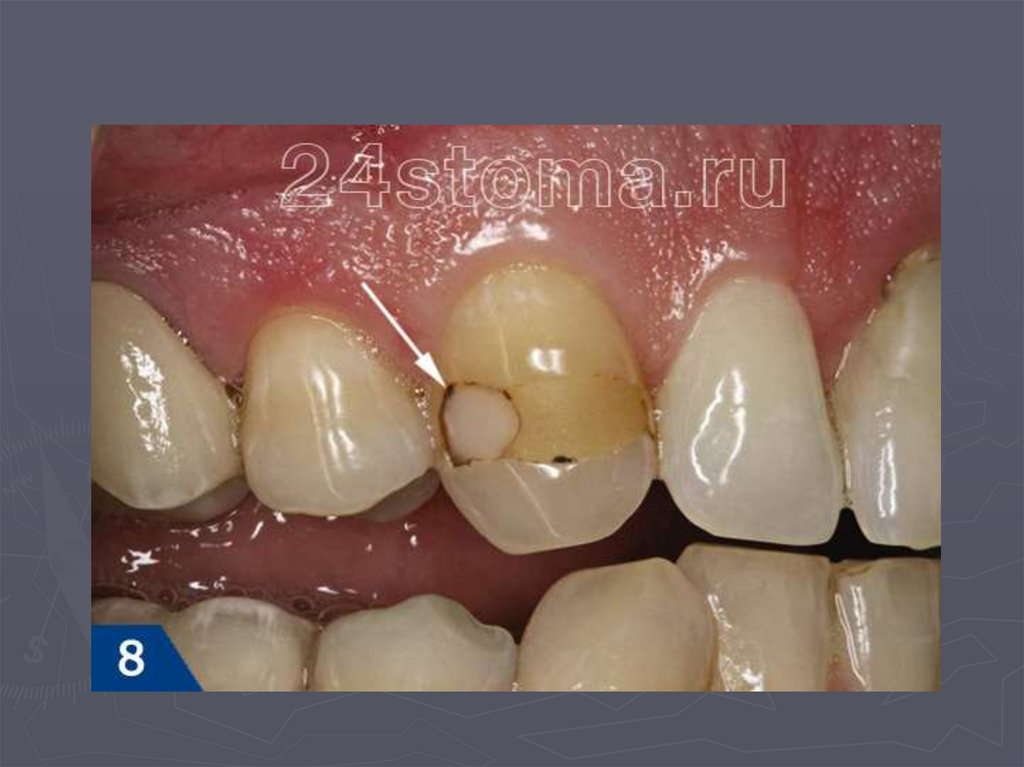

38. КЛИНИЧЕСКАЯ КАРТИНА СРЕДНЕГО КАРИЕСА при декомпенсированной форме:

► при локализации кариозной полости в фиссурах

определяется небольшое входное отверстие;

► при раскрытии обнаруживается кариозная

полость с податливым дентином;

► края кариозной полости нависают;

► эмаль тонкая, хрупкая;

► дентин светлый, влажный, размягченный, легко

удаляется экскаватором;

► зондирование болезненно по

эмалево-дентинному соединению.